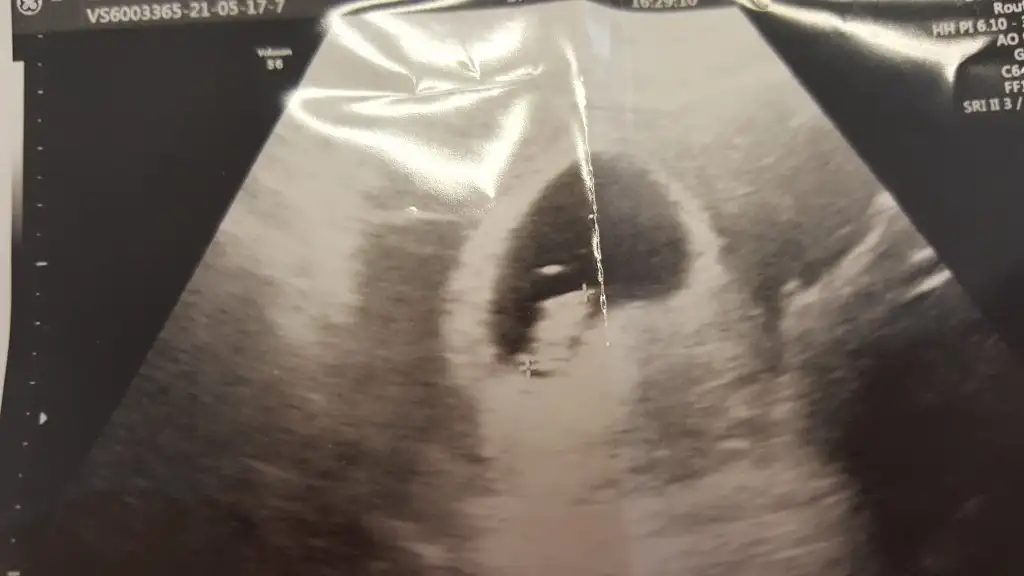

Sağ olasın. Ben göremedm ama şüphen devam ediyorsa kanda baktır bi istersen?